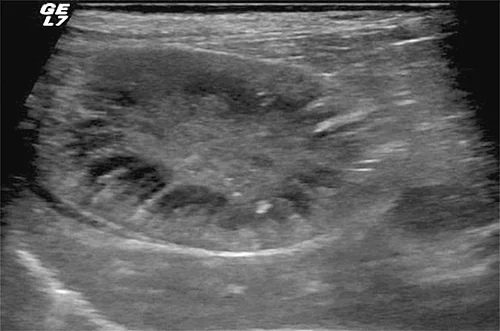

Bei der Sonografie liegt die GB rechts der Medianen und ist in der Regel mittels subkostaler Anschallung gut erreichbar. Im sonografischen Normalbefund stellt sich die GB in der Längsachse als birnenförmige und im Querschnitt als runde anechogene dünnwandige Struktur dar (Abb. 1). Bei tiefbrüstigen Patienten, kleiner Leber und hochdorsaler Lage der GB bedarf es vereinzelt der transinterkostalen Anlotung. Aufgrund der geringen Auflagefläche und des Frequenzspektrums im Bereich um 8–12 MHz sind daher Mikrokonvexsonden besonders für die Untersuchung geeignet.